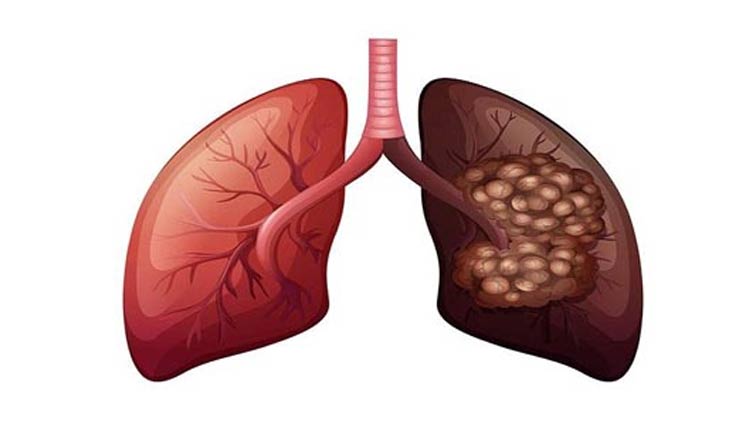

फेफड़े हमारे शरीर का एक महत्वपूर्ण अंग है जिसके बिना हमारा जीवित रहना असंभव है क्योंकि इसका काम हवा से ऑक्सीजन को अलग करके रक्त में पहुंचना होता है। हमारे शरीर से कार्बन डाईऑक्साइड पैदा होती है, जो फेफड़ों के द्वारा शरीर से आसानी से बाहर निकल जाती है। लेकिन कई बार हमारे शरीर में संक्रमण होने लगता है। जिसके कारण हमारे फेफड़े सही से काम नहीं करते और खराब होने लगते हैं। जो फेफड़े के कैंसर का रूप धारण कर लेते हैं।यह बीमारी आजकल बहुत ही ज्यादा बढ़ गयी है जिससे कई लोग ग्रसित होते है। यह समस्या पुरुष या महिला दोनों में से किसी को भी हो सकती है। तो आइये जानते है इसके लक्षण, कारण और बचाव के बारे में.....